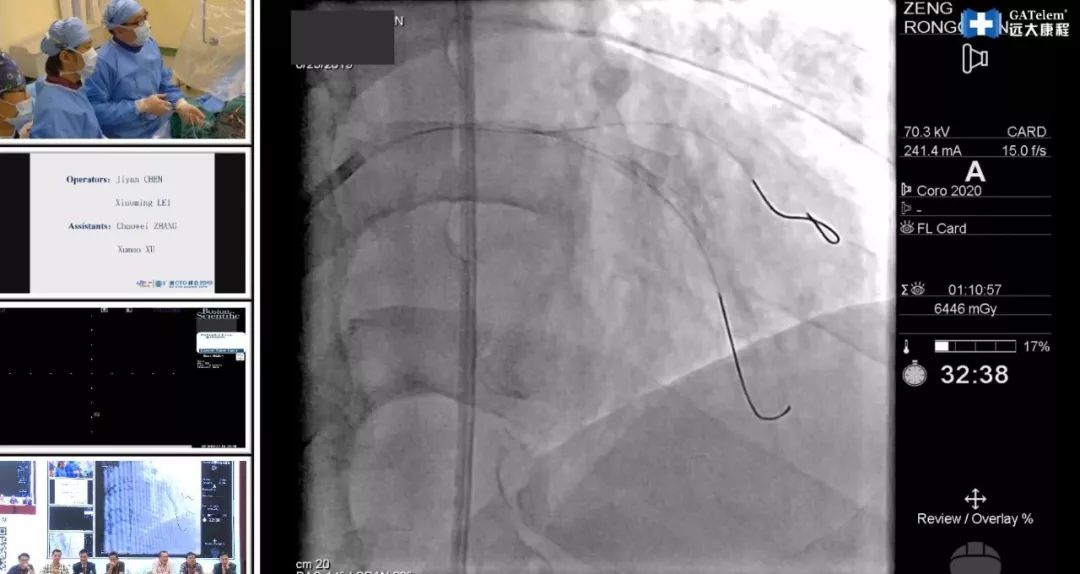

8月23日下午,广东省人民医院陈纪言主任及广州市第一人民医院雷晓明教授带来第四台病例的手术演示。中山大学附属第一医院杜志明教授,空军军医大学西京医院胡涛教授,广东省人民医院于汇民教授,江门市中心医院彭宇程教授,四川省人民医院陈勇教授,南方医科大学珠江医院缪绯教授,河北省沧州市中心医院宋坤青教授,佛山市第一人民医院许兆延教授担任会议主持并进行病例讨论。

该患者前降支完全闭塞,且存在对角支的干扰。J-CTO评分为2-3分,此次手术为第三次手术。该闭塞段不长,为齐头闭塞,闭塞段远端血管出现弥漫性病变。该患者心外膜侧支居多,对角支和前降支在心尖部形成侧支循环,但非常迂曲。

专家组一致认为,逆向开通CTO风险较大,选择正向做CTO开通成功的可能性相对较大。随后专家组就导丝的选择问题进行了探讨。手术过程中,陈纪言教授表示,在做正向尝试的同时也应做好逆向开通CTO的准备。双侧造影后,首先选用Gaia 2进行正向尝试,由于导丝进入螺旋夹层,故随后采用平行导丝技术,成功穿刺。

第二根导丝选用Gaia 3在远端血管较薄弱的地方进行正向尝试。经过几次导丝升级依旧失败后,采用逆向技术。首选一个小的同侧对角支作为逆向通道,并选用Gaia 3做Reverse-CART。逆向导丝成功进入正向导管后,通过微导管建立双导丝。随后遇钟乳石样的钙化部位时,采用小球囊扩张后使导丝成功通过。最终成功放置支架并实现导丝实现对吻。

专家组表示,此次陈主任为大家带来了一台非常精彩的病例,不仅在进行前向开通CTO的过程中尝试了不同的方法,在通过同侧对角支进行逆向开通CTO的过程也十分精彩,堪称教练式的手术演示。